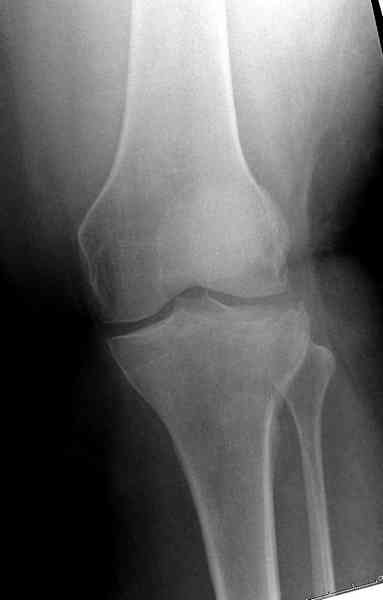

Здравствуйте, уважаемые коллеги!Подскажите, пожалуйста, какой выбрать доступ и способ фиксации при импрессионном переломе заднего отдела наружного мыщелка большеберцовой кости. Женщина 40 лет, травму получила 02.01.2008, катаясь на горных лыжах.Есть ли здесь необходимость использовать задний доступ, или можно справиться через наружный? Есть ли шансы сделать закрыто - под ЭОП через медиальное "окошко" поднять забойником суставную поврехность? Какой лучше использовать фиксатор?Спасибо.

Из медиального окна можно приподнять латеральную

импрессию. Фиксация тремя параллельными шурупами в

эпифизарной части над импрессией. Создается крыша,

которая предупредит коллапс. На образовавшуюся полость - костная пластика из аутокости или синтетический заменитель. Мы применяем Osteoset в 4-5 мм диаметре таблеточки или иньекционную форму Prodens.